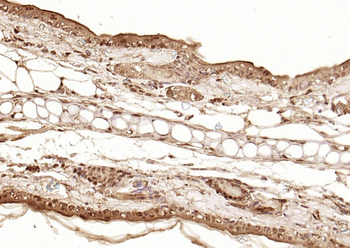

50 μl, 100 μlPhospho-Smad3 (Thr179) Rabbit Polyclonal Antibody [orb313112]

FC, ICC, IF, IHC-Fr, IHC-P

Bovine, Canine, Equine, Porcine, Sheep

Human, Mouse, Rat

Rabbit

Polyclonal

Unconjugated

100 μl, 200 μl, 50 μlSMAD7 Rabbit Polyclonal Antibody [orb500819]